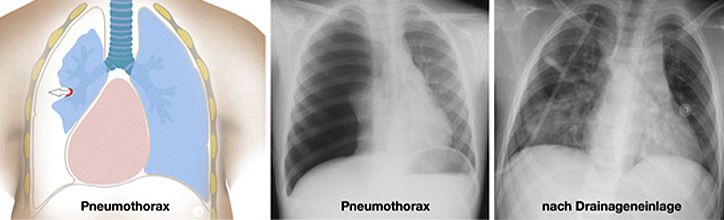

Grundlegender Unterschied beim Kind verglichen mit dem Erwachsenen, ist die geringere Körpergröße und Masse sowie die hohe Plastizität der knorpeligen Rippen. Diese frakturieren (brechen) beim stumpfen Thoraxtrauma in der Regel nicht, leiten aber die Kraft der Gewalteinwirkung vielmehr auf die darunter liegenden Strukturen fort. Folge können Gewebezerreissungen der Lungenstrukturen sein mit der Folge von Blutungen, Ödembildung, Pneumo- oder Hämatothorax (Abbildung)